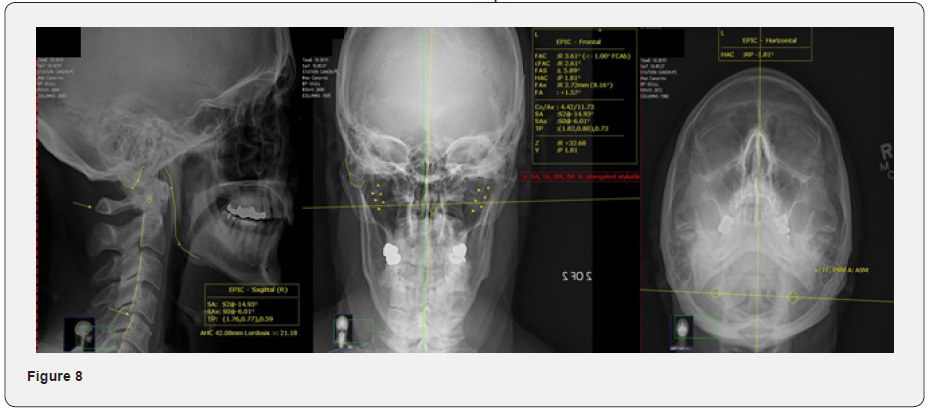

The EPIC radiographic analysis currently evaluates for 23 genetic asymmetries and/or anomalies to determine what a patient’s “normal” structural position should be. The EPIC analysis additionally measures four multi-directional misalignments through computerized analysis to determine the biomechanics of vertebral misalignment, the degree-specific line of drive for the adjusting trajectory, and the targeting location for the impulse.

The four multi-directional misalignments measured are:

- C1 (atlas) to occiput rotational malposition around the Z axis (ØZ)

- C1 (atlas) to cervical spine rotational malposition around the Z axis (ØZ)

- C1 (atlas) rotational malposition around the Y axis (ØY)

- C2 (axis) rotational malposition around the Y axis (ØY)

Due to the fact that the analysis coordinate measurements are within 1/100th of a degree, the accuracy of analysis directly equates to a decreased potential for error in the adjusting angle. With increased accuracy in the adjusting angle and targeting of the impulse, the amount of force used to accomplish the adjustment can be minimized. This accuracy also equates to only requiring a single impulse for the correction (Figure 8). The radiographic analysis also determines the biomechanical influences necessary for positioning the patient prior to the adjustment in order to minimize joint resistance and influence the four misalignments to reduce proportionately and equally with a single, correctional impulse.